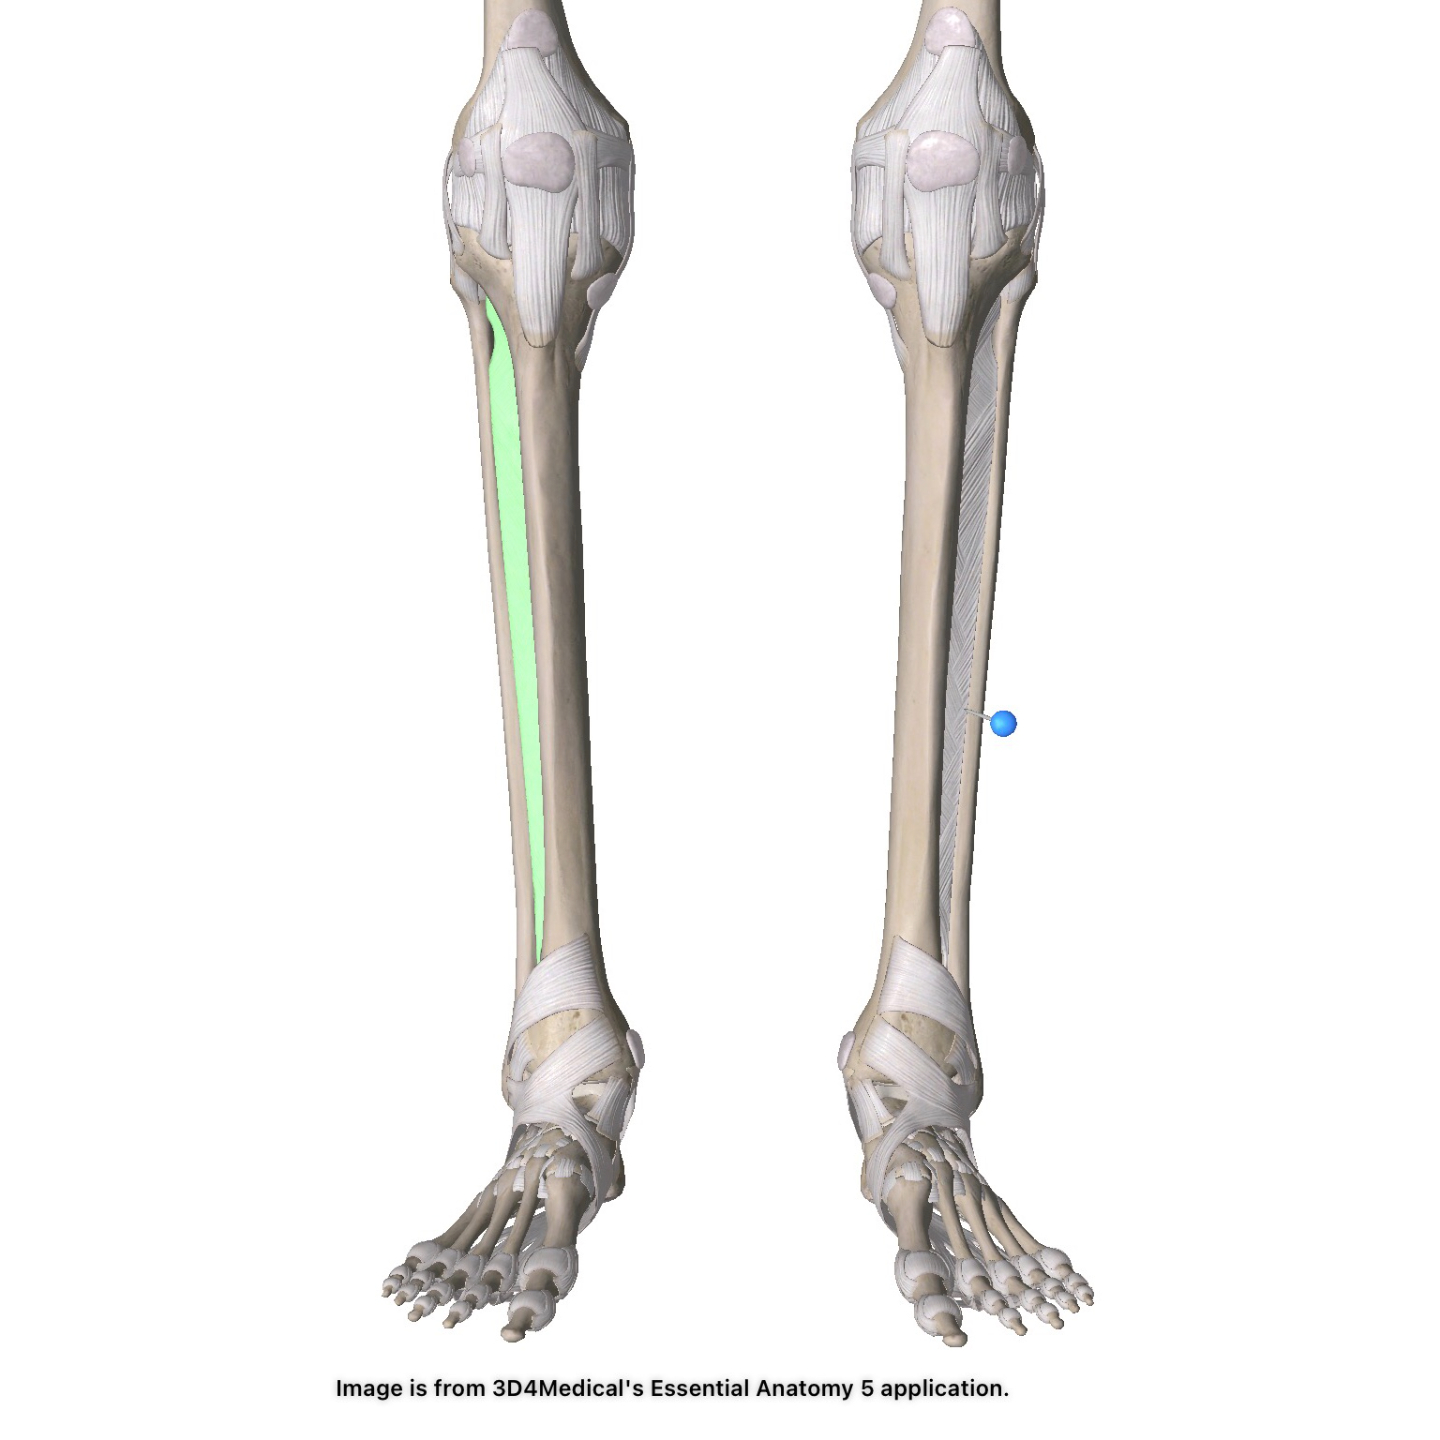

Ankle Sprains: 3 Steps Physicians Should Follow

Ankle sprains are one of the most common orthopedic injuries. When working with patients, physicians should follow these three steps in order to get the patient back into action quickly and safely.